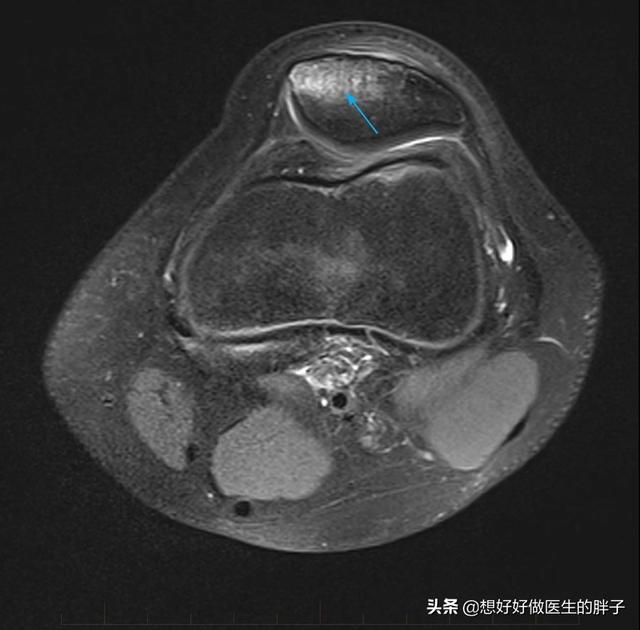

髌骨挫伤在临床上是相对来讲比较常见的,这种损伤机制多见于在运动过程当中摔倒膝盖着地,髌骨与地面相撞的过程当中虽然*力暴**没有导致整个髌骨的离断,但是导致髌骨内发生了细小的骨折,我们称之为微骨折,这种情况在核磁上表现出来的影像学表现称之为骨挫伤,下图就是典型的髌骨挫伤的影像学表现。

骨挫伤 箭头所指为明显挫伤区域,瘀血和水肿核磁表现

虽然*力暴**没有导致整个髌骨的骨折,但是*力暴**传导到髌骨内部以后,造成了髌骨内骨小梁的细小骨折,这样骨折以后就会有水肿、有出血,所以在核磁眼镜上是高亮的表现,在上图当中箭头所指的部位就是骨损伤的部位。

不同于髌骨骨折,这种情况一般在x线上是无法看出来的,核磁是发现骨挫伤最佳的手段之一。因为骨折以后在x线上会有明显的骨折,形态改变,但是在骨挫伤的情况下,整体的髌骨形态是完整的,X线并不能很好的表现出髌骨内部的损伤情况,所以此时我们要动用核磁出场。